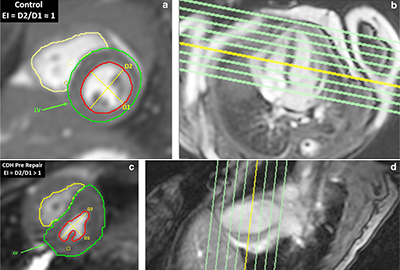

Neonatal MRI

The goal of this research is to translate new and innovative MRI techniques to sick and challenging patient populations, like those that are born prematurely. Our studies include both proton MRI and hyperpolarized gas MRI in infants. This has begun to revolutionize our understanding of both parenchymal and airway components of disease. This research is being conducted in partial collaboration with the BPD Center.